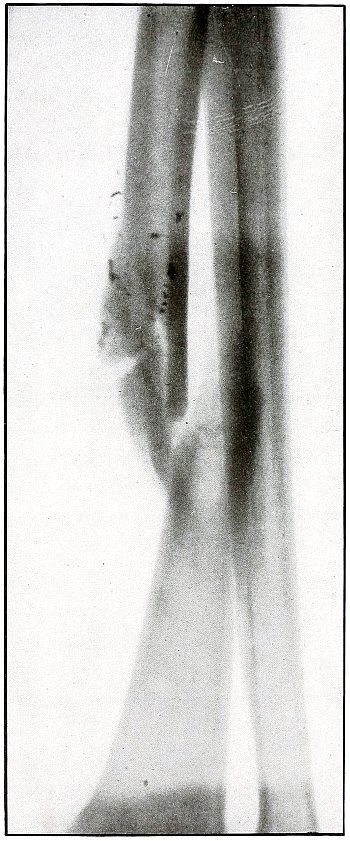

| 35. |

Gunshot fracture, ulna |

80 |

| 36. |

Gunshot fracture, ulna |

82 |

| 37. |

Gunshot fracture, ulna |

84 |

| 38. |

Gunshot fracture, ulna |

86 |

| 39.[Pg 4] |

Gunshot fracture, ulna |

88 |

| 40. |

Gunshot fracture, ulna |

90 |